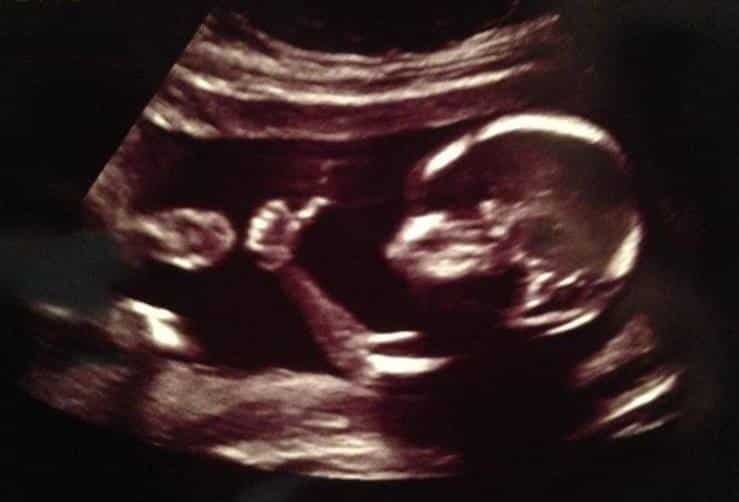

Questo è sicuramente il punto nodale: quando inizia la vita umana? ( leggi qui il nostro articolo). Ormai la scienza è unanime nel ritenere che al momento del concepimento c’è un nuovo essere vivente, completamente diverso dal padre e dalla madre che lo hanno generato. Il DNA di un embrione è unico e irripetibile e da lì in poi si svilupperà in un continuum senza interruzione alcuna. Embrione, feto, neonato, bambino, ragazzo, uomo, anziano, sono definizioni diverse per indicare la stessa persona. Se non si interviene, con violenza, dall’esterno, sul processo di sviluppo, la microscopica cellula di partenza, lo zigote, arriverà al parto e nascerà un piccolo. Di conseguenza, l’aborto è esattamente un omicidio.

Non si tratta solo di un fatto fisico, biologico: “rimuovere un feto da una femmina”, come sostengono gli abortisti, significherebbe attribuire all’atto abortivo una semplice valenza meccanica. Intanto è dimostrato che un feto sente dolore anche nel primo trimestre di gravidanza, ed è bene essere consapevoli che il piccolo percepisce la violenza dell’atto abortivo. Ma non solo: una donna ( come gli uomini) ha un corpo, un’anima, una mente. Strappare il bambino dalla pancia di una madre significa senz’altro causarle un dolore all’anima  che si protrarrà per decenni. Nessuno più disconosce l’esistenza della sindrome post abortiva, che affligge la madre mancata al punto da causarle danni psicologici spesso profondi, tanto da richiedere l’intervento di terapisti per ricostruirle l’autostima e l’equilibrio. Chi può pensare che la donna abortisca in modo spensierato? Chi può credere che la donna sia un mostro di insensibilità? Allora, come si può spingere la donna ad abortire per esercitare la propria libertà assoluta? Vuol dire non voler il bene di quella persona.( leggi qui e qui i nostri articoli)